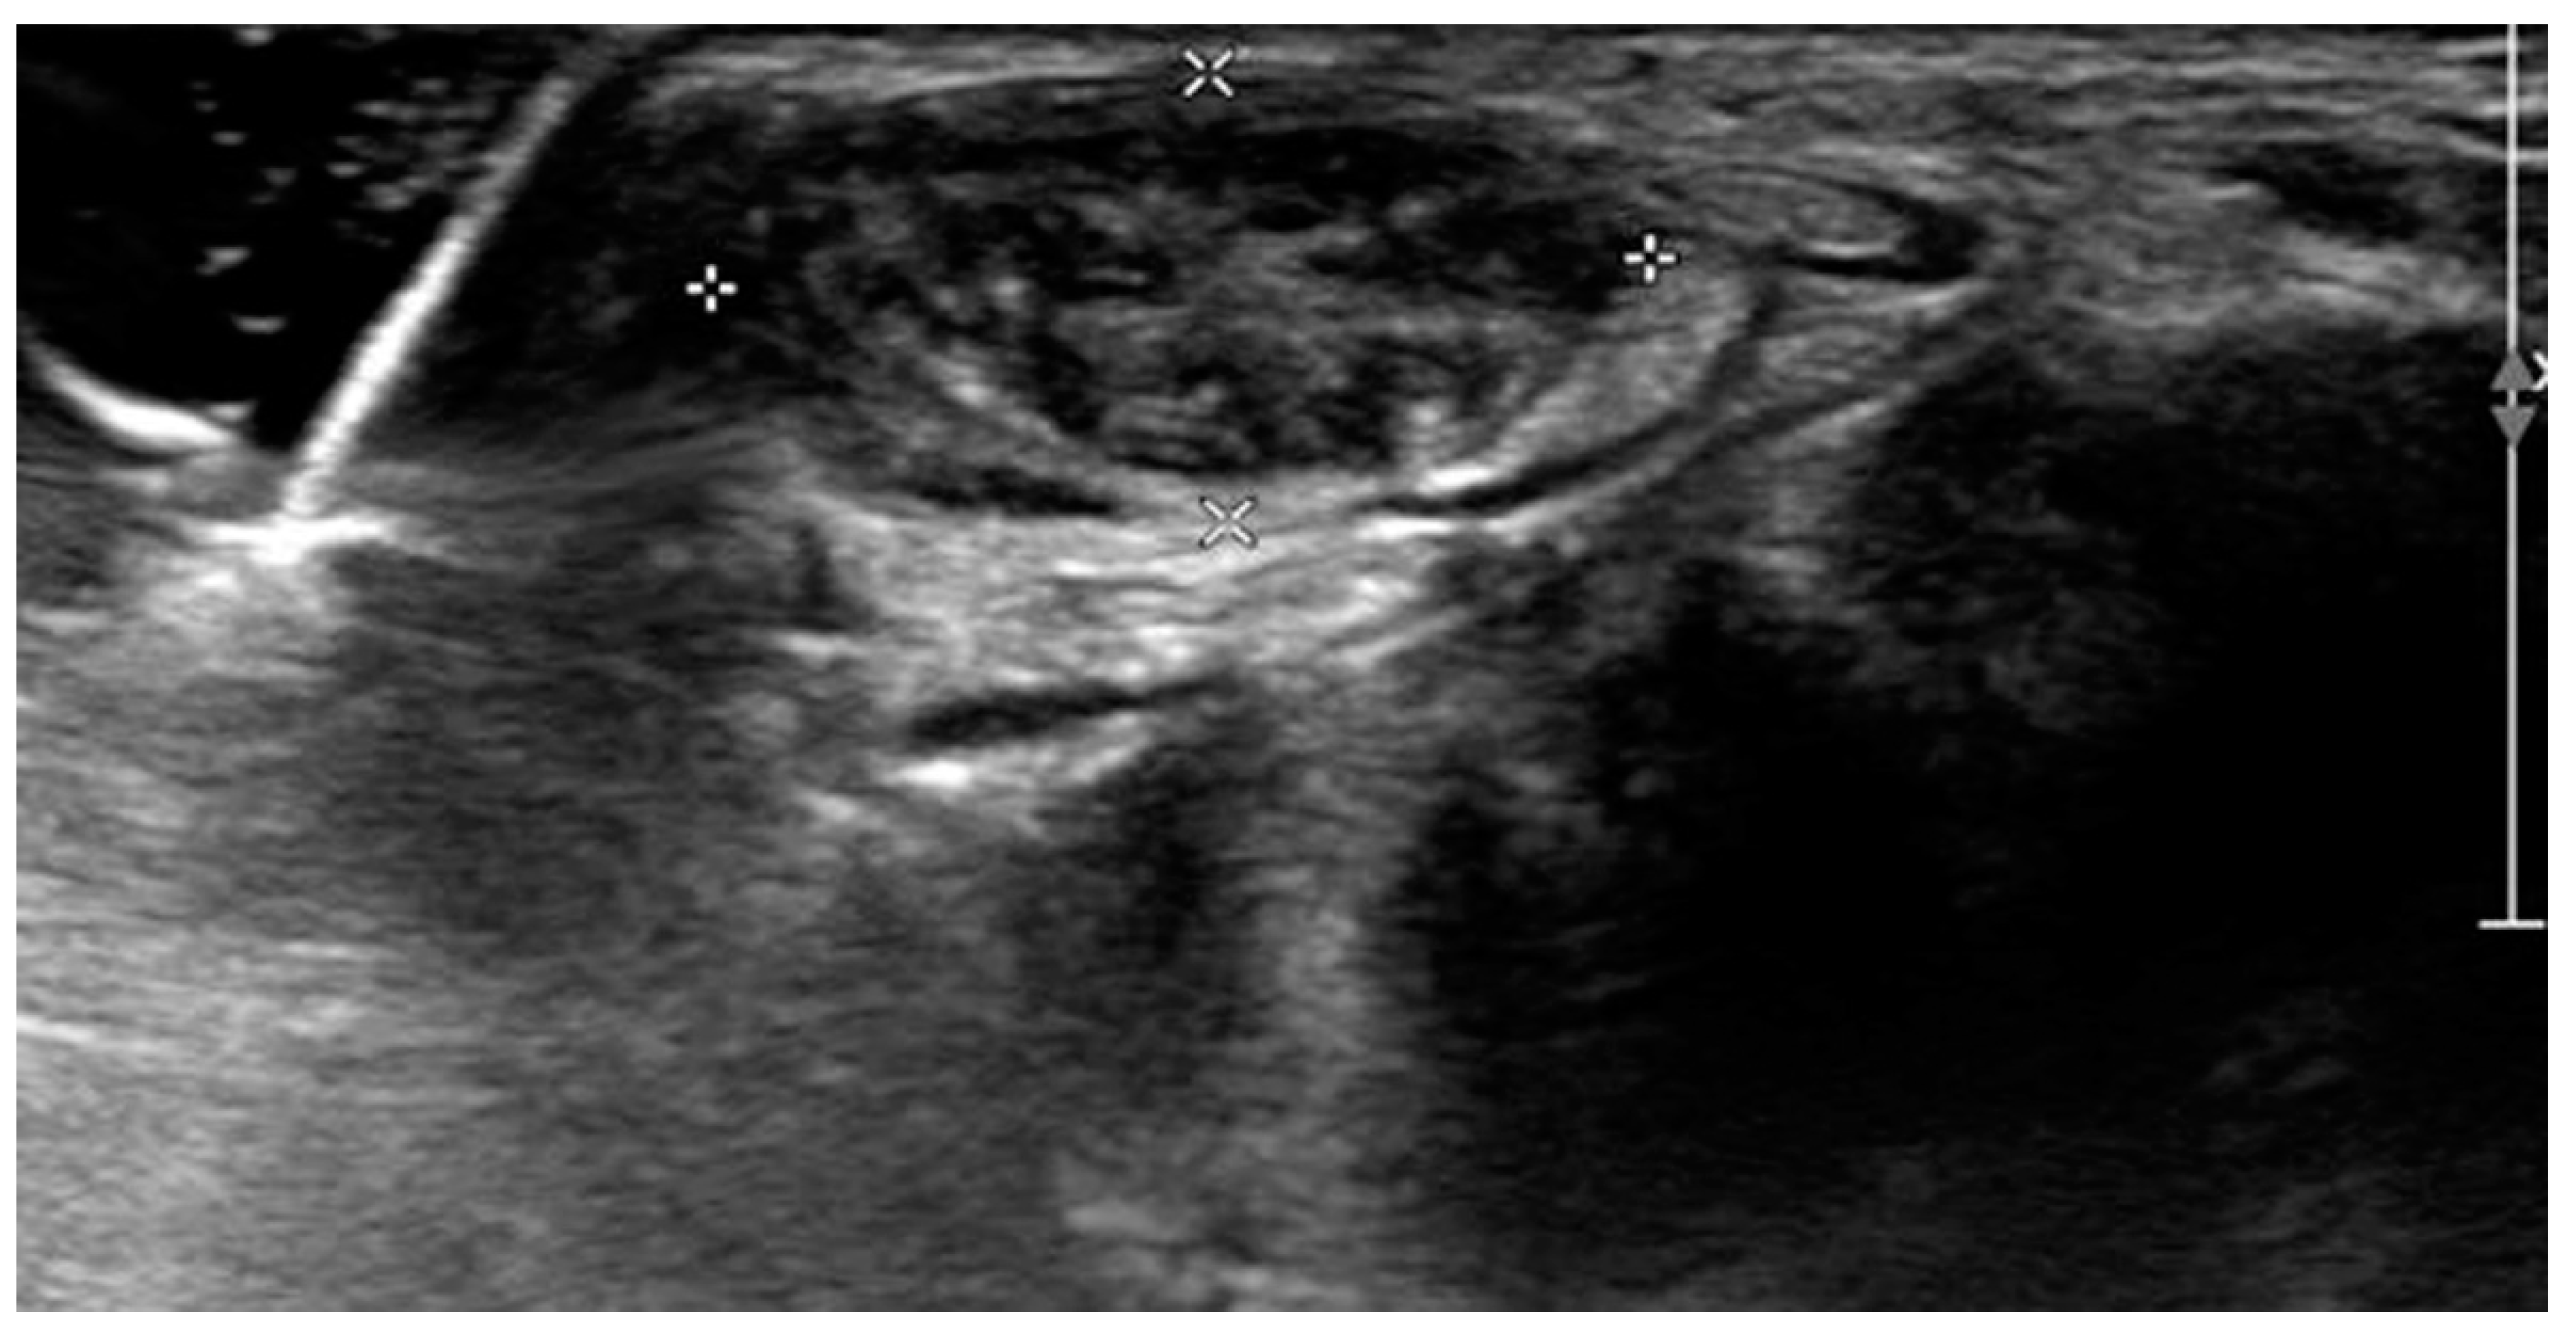

Ultrasonographic examination on the first visit to the clinic showed severely edematous and hypertrophied median nerve from the left wrist level down to the palm with low-echogenic intraneural multiple fascicles (Figure 2). In addition, subsequent enhanced magnetic resonance imaging of the left wrist indicated fusiform enlargement the median nerve from the left forearm distal 1/3 area down to the left hand metacarpal area along with characteristic findings of longitudinally-oriented cable-like appearances of the tumor in addition to its invasion into flexor retinaculum Figure 3).

In the diagnosis of LFH, MRI plays a critical role by offering pathognomic radiologic features, low-intensity serpentine nerve fibers embedded in abundant high-intensity adipose and fibrous tissues, also known as “cable-like appearances”.[9] In addition, ultrasonography also serves an essential tool for initial diagnosis and postoperative non-invasive radiologic follow-ups. Ultrasound imaging of LFH is characteristic of the enlarged cross-section of the affected nerve with hypoechoic fascicles embedded in the hyperechoic fibrous and adipose tissues, and recent ultrasonography has shown to provide as equivalent diagnostic evidence as MRIs.[10] While MRIs are beneficial in assessing the extent of the lesion in the initial diagnosis, ultrasonography serves a critical role in serial postoperative follow-ups, as seen in the current case description. However, biopsy and histologic examinations are the only definitive measures for the diagnosis of LFH, which are characteristic of intertwining collagen, fibroblasts, and adipose cells separating nerve fascicles and infiltrating the space between the epineurium and perineurium without inflammation or myelin degeneration.[2]

Figure 2. Wrist ultrasonography shows thickened and hypoechoic intraneural fascicles (white crosses).